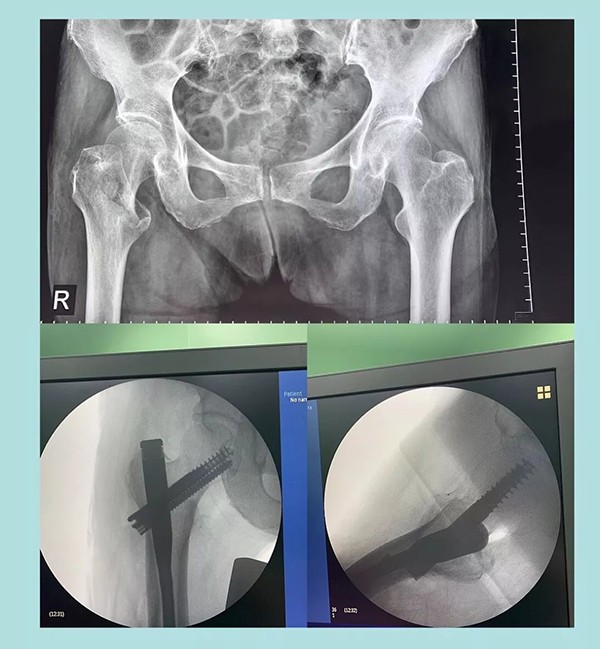

幾天前,蒲奶奶不小心摔了一跤倒地不起,到家附近醫(yī)院檢查后被診斷為右側(cè)股骨粗隆粉碎性骨折。醫(yī)生告知家屬,這種骨折對(duì)于老人來說非常棘手,建議保守治療。為提高老人生活質(zhì)量,家人商量后決定放手一搏,在打聽到我院關(guān)節(jié)科對(duì)這種病例治療效果非常理想后,立即轉(zhuǎn)往我院。

經(jīng)過內(nèi)科疾病的治療調(diào)理,總體符合手術(shù)條件后,羅軍主任帶領(lǐng)手術(shù)團(tuán)隊(duì)為老人實(shí)施了閉合復(fù)位Intertan髓內(nèi)釘微創(chuàng)手術(shù)。為避免全麻對(duì)肺功能的影響,術(shù)中沒有使用常規(guī)的全麻氣管插管,而是采取神經(jīng)阻滯麻醉。術(shù)前老人嚴(yán)重貧血,為盡可能減少術(shù)中出血,手術(shù)采用微創(chuàng),且在半個(gè)小時(shí)內(nèi)順利完成。術(shù)后老人沒有明顯疼痛,術(shù)后一周即下地行走。